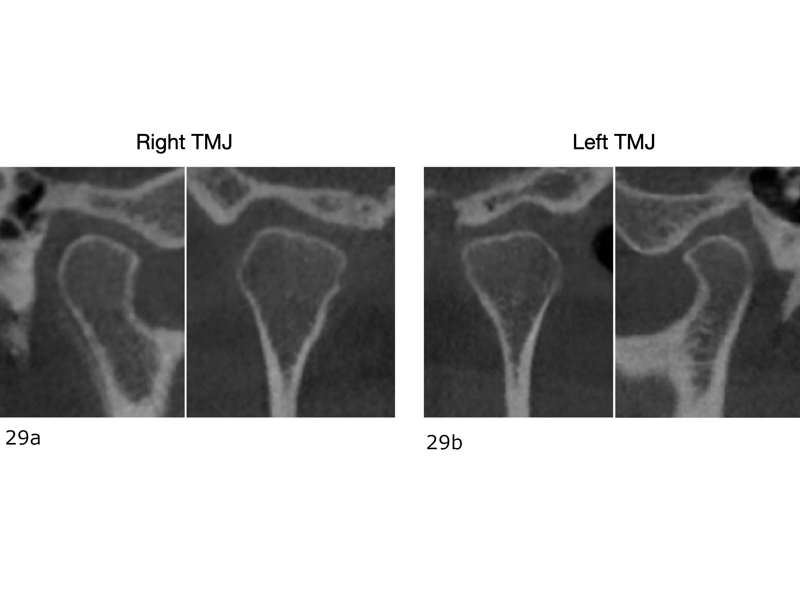

The final dental panoramic tomogram showed the correct levelling of the occlusal planes and root positions (Fig. 26). The final cephalometric tracing showed closure of the facial angle thanks to the posterior intrusion and mandibular auto-rotation (Figs. 27 & 28). Mandibular antero-rotation shortens the lower facial third, improving lip competence and ultimately the facial profile. The CBCT images of the TMJs showed the correct position of the condyles within the glenoid fossae (Fig. 29). When looking at the airway on the CBCT scan, we also saw an improvement of the patient’s airway (Fig. 30).